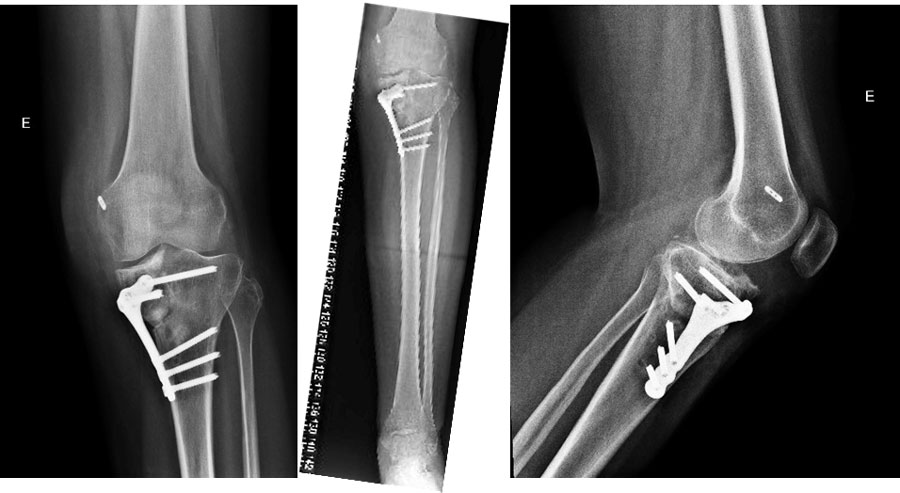

Pre-op Xrays

Pre-op Xrays​

In view of the lateral radiography, which test(s) do you expect to be positive in your physical examination?

• ✔️ Reverse pivot shift test

• ✔️ Posterior sag sign

The lateral X-ray shows a posterior displacement of the tibia due to a PCL torn. In those cases, you should find a positive reverse pivot shift test and a posterior sag sign